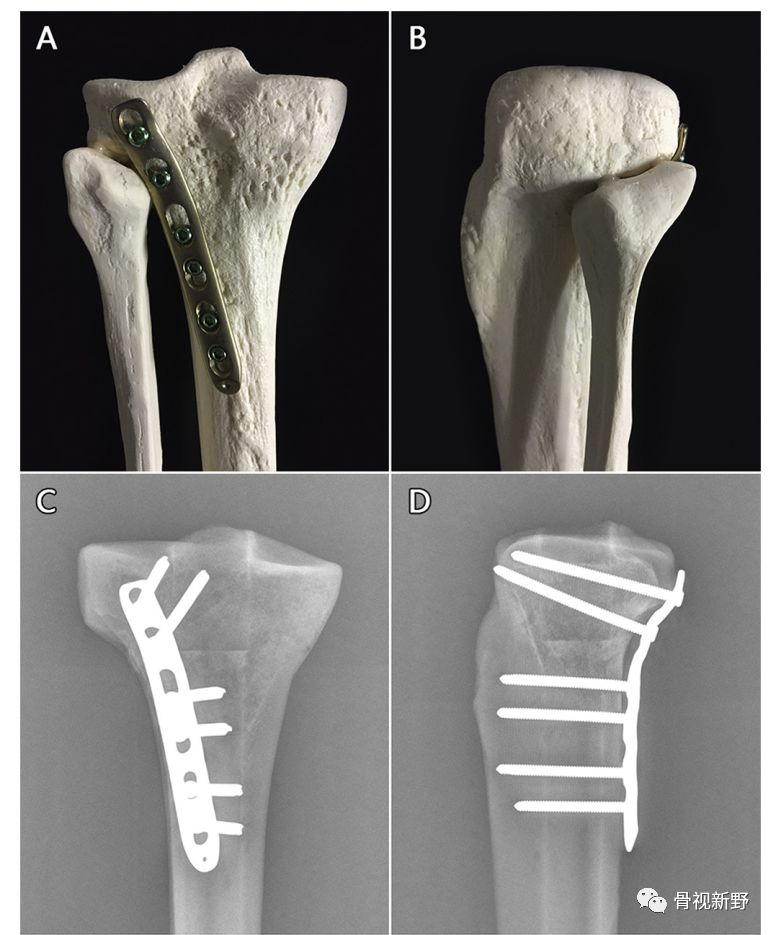

胫骨平台骨折的buttress固定

按照三柱理论,胫骨平台可分为外侧柱、内侧柱、后柱(后外、后内)。胫骨平台后柱骨折(尤其屈膝损伤者),由于骨折块存在较大的垂直剪力,往往需要buttress钢板作防滑固定,以对抗骨折块向下滑移的剪切力。

后外侧柱buttress钢板(Knee. 2018 Apr 17. pii: S0968-0160(18)30140-6)

三柱buttress钢板

除后柱骨折需要buttress钢板固定外,内、外侧平台塌陷、劈裂骨折常规所使用的钢板其实也是一种支持钢板。因此,笔者认为,胫骨平台骨折的内、外、后三柱均是buttress钢板的固定原理,防滑或支撑。